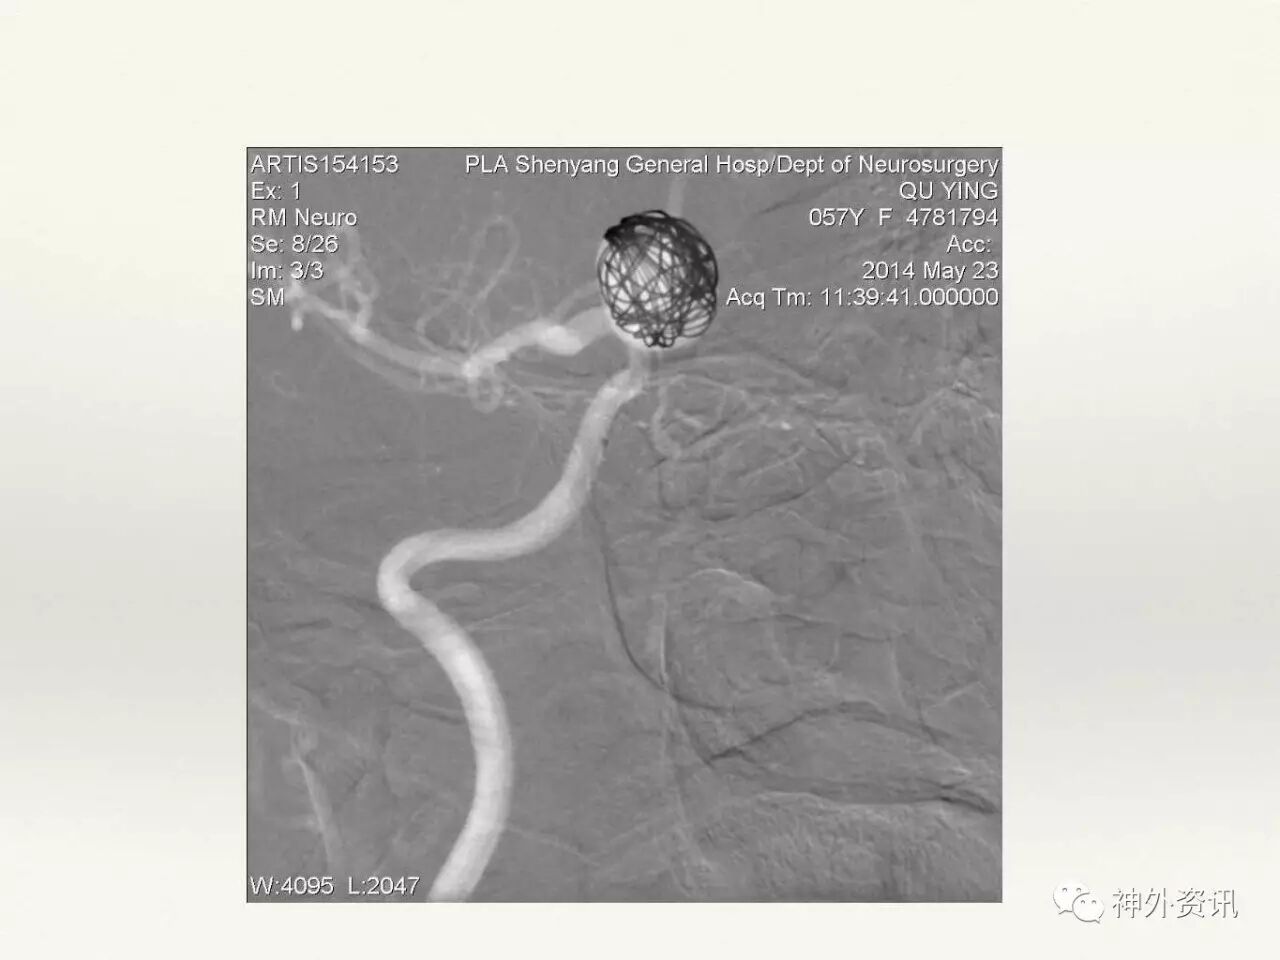

在东北地区率先开展了颈内动脉、大脑中动脉及基底动脉闭塞血管内再通、颅内动脉栓塞急性期取栓、血流导向装置治疗大型宽颈动脉瘤等,对颅内动脉瘤、动静脉畸形、颈动脉及颅内动脉狭窄、颈内动脉海绵窦瘘、硬脑膜动静脉瘘等外科治疗具有较深的造诣。完成脑血管造影8600余例,各类脑血管病介入手术共4500余例,动脉瘤、动静脉畸形、脑肿瘤、脑出血及脑外伤等外科手术1500余例。